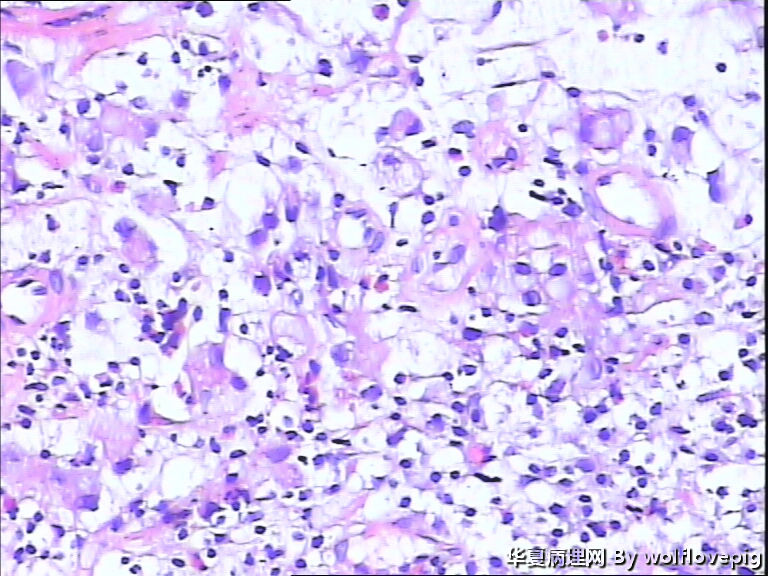

男,60y,胃窦呈结节样改变。

图3